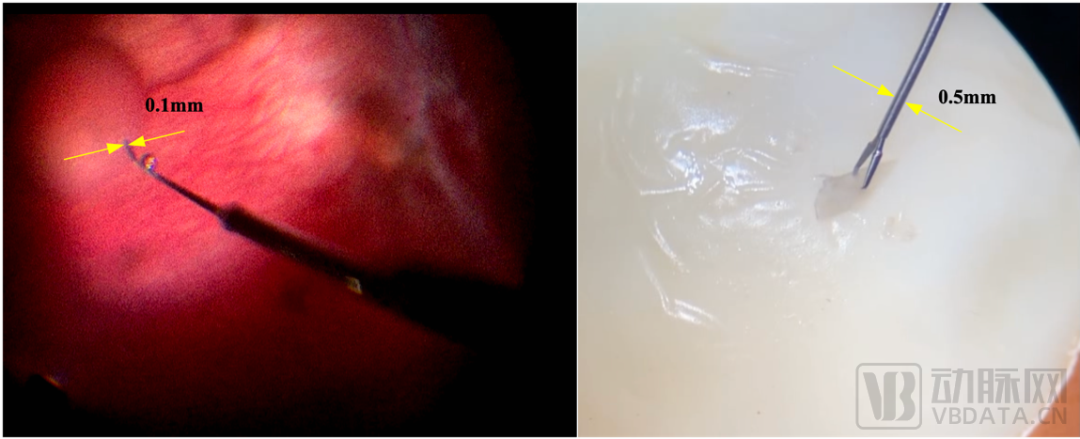

圖左:醫(yī)生操控迪視機(jī)器人用于活體兔視網(wǎng)膜下腔注射;圖右:醫(yī)生操控迪視機(jī)器人用于20μm厚的雞蛋薄膜剝離

據(jù)悉,迪視醫(yī)療布局研發(fā)的顯微外科手術(shù)機(jī)器人擁有近20個超高自由度,能夠輔助顯微外科醫(yī)生完成各種高難度、超顯微精細(xì)靈巧操作,例如吻合直徑范圍為0.3~0.8毫米的淋巴管、血管或者神經(jīng),在耳鼻喉、淋巴外科、神經(jīng)外科、整形外科等多科室均有重大應(yīng)用價值。

經(jīng)過術(shù)前詳細(xì)檢查和精心準(zhǔn)備,手術(shù)當(dāng)天,由浙江省人民醫(yī)院眼科中心沈麗君教授,陳亦棋教授領(lǐng)導(dǎo)的眼底病手術(shù)團(tuán)隊,操作“迪視微鋒”眼科手術(shù)機(jī)器人,通過外徑100微米的顯微注射針,在3分鐘內(nèi)將400微升溶栓藥物重組組織纖溶酶原激活劑(rtPA)精準(zhǔn)地注射到了患者眼底視網(wǎng)膜下腔中。術(shù)中OCT結(jié)果顯示,藥物被精確遞送至病灶部位,按照治療計劃成功地駐留在網(wǎng)膜色素上皮層上方的下腔中。整個手術(shù)操作流暢、穩(wěn)定、精準(zhǔn)。